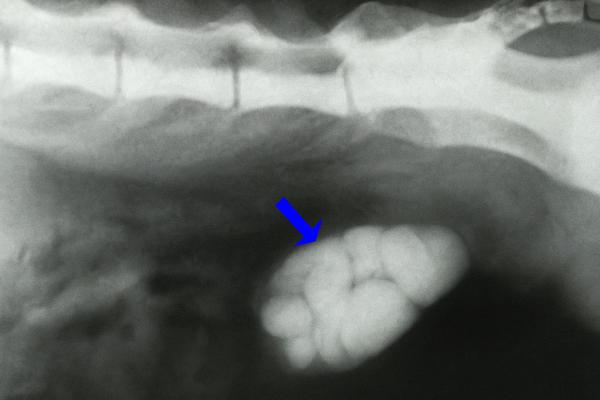

5. Cálculos renales

Los cálculos o nefrolitos renales en gatos son depósitos duros de minerales que se forman dentro de los riñones y pueden causar daños graves en el órgano afectado. Aunque los nefrolitos renales son menos frecuentes que los vesicales, también pueden aparecer debido a alteraciones en la concentración de la orina o en su pH, a dietas con exceso de minerales, a baja ingesta de agua o a predisposición genética.

En la especie felina, los cálculos más comunes son los de oxalato cálcico, que son duros, no se disuelven y predominan en el riñón, y los de estruvita, que contienen fosfato amónico-magnésico y suelen formarse más frecuentemente en la vejiga.

Los cálculos renales pueden provocar síntomas como dolor abdominal o lumbar, hematuria, vómitos, micción frecuente o dificultosa, letargo e incluso anorexia.

El tratamiento de los cálculos renales depende en gran medida del tipo de cálculo:

- Los cálculos de estruvita pueden disolverse mediante dieta renal.

- Los cálculos de oxalato cálcico suelen requerir cirugía, ya sea mediante nefrotomía o ureterotomía en caso de obstrucción grave del flujo de orina. En centros especializados, también se puede realizar una intervención llamada litotricia, que consiste en la fragmentación de los cálculos mediante láser o ultrasonido.

Además, es importante aumentar la hidratación del gato, controlar el dolor y proporcionar soporte renal en los casos en los que la función del riñón esté gravemente comprometida.